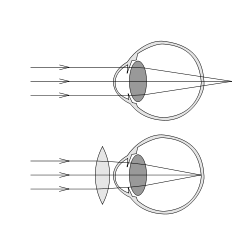

எட்டப் பார்வை (Hyperopia) என்றும் தூரப் பார்வை (longsightedness அல்லது hypermetropia) என்றும் அறியப்படும் கண்ணின் குறைபாடு விழிக்கோளமோ விழி வில்லையோ செம்மையாக இல்லாமையால் உருவாகிறது. இக்குறைபாட்டினால் அண்மையிலுள்ள பொருட்களைக் காண்பதில் சிரமம் ஏற்படுகிறது. விழியின் அண்மைப் பார்வைக்கான குவிமையத்தன்மை ஆற்றல் குறைகிறது. சில தீவிரமான குறைபாடுகளில் எந்த தொலைவிலுள்ள பொருளையுமே குவியப்படுத்த இயலாது போகலாம். ஓர் பொருள் கண்ணின் அருகே வரும்போது நலமான கண்ணின் வில்லையானது தனது வலுவை கூட்டிக்கொண்டு பொருளின் படிமத்தை விழித்திரையில் படியச் செய்யும். ஆனால் கருவிழி மற்றும் கண்வில்லையின் வலு குறைந்து இவ்வாறு ஏற்ற இயலாவிடில் எட்டப் பார்வை குறைபாடு ஏற்படுகிறது. இதனால் பொருளின் படிமம் விழித்திரைக்குப் பின்னால் உள்ளதொரு புள்ளியில் குவியப்பட்டு தெளிவின்றித் தெரியும்.

இக்குறைபாடு மரபுவழியாக மிகச்சிறிய கண் அல்லது தட்டையான கருவிழியிருப்போருக்கு ஏற்படுகிறது. இதனை குழி வில்லை கொண்ட மூக்குக் கண்ணாடிகள் மூலமோ தொடுவில்லைகள் மூலமோ சரியாக்கலாம்.